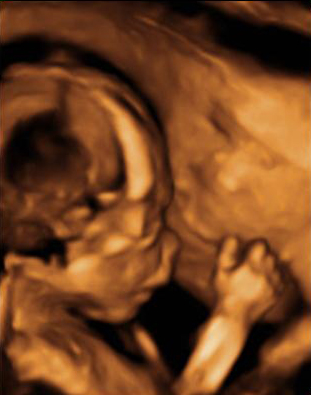

En esta imagen obtenida con una ecografía en 4D de un feto de 20 semanas de gestación se contempla cómo el bebé mueve sus brazos delante de su cara. Aún se encuentra muy delgado, ya que es a partir del tercer trimestre, sobre todo, cuando el feto empieza a acumular grasa bajo su piel.

Ecografía de bebé de 20 semanas de perfil

Podemos ver claramente los miembros superiores: el feto flexiona los brazos y los pasa por delante de la cara